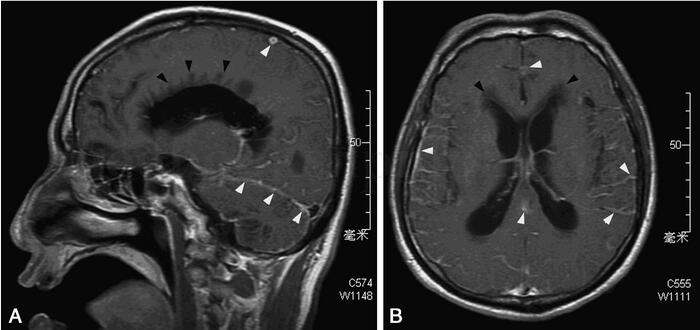

1小时条评论癌性脑膜病常由于血液系统恶性肿瘤或腺癌弥漫性浸润软脑脊髓、神经鞘或脑实质,引起颅内压增高及局灶性神经损害。这一疾病的特点是什么?确诊需要进行哪些检查?作者通过3例典型病例一一为大家解答。 临床资料 病例1 男性,52岁,干部,内蒙古籍。因头痛3个月于200...